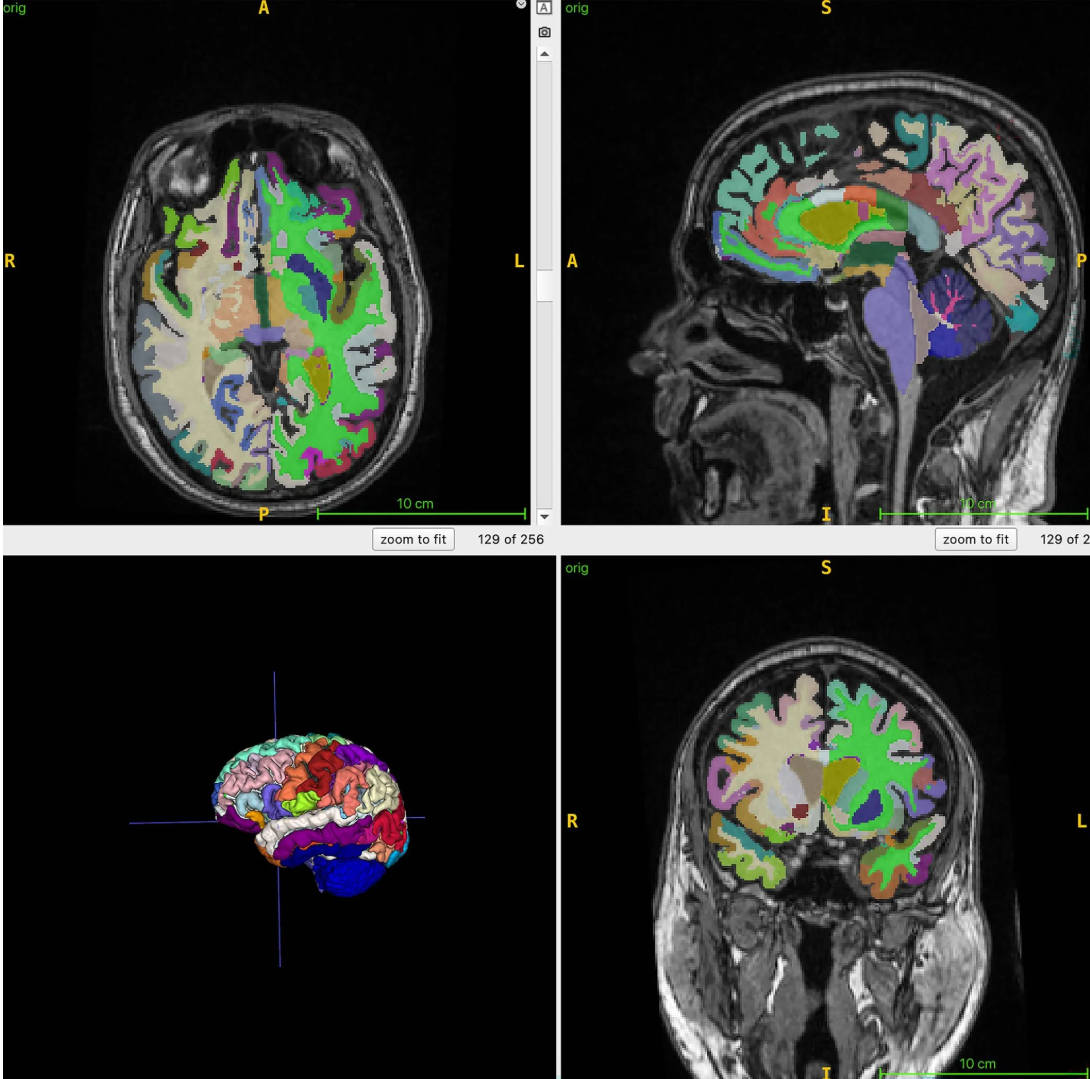

▲ 图源:Cyrus Raji 博士科学家首先对 1164 名健康成年人进行全身核磁共振成像扫描,其中女性占比 52%,平均年龄 55.17 岁,研究使用 T1 加权 MRI 序列,可清晰展现肌肉、脂肪和脑组织,并使用 AI 测量受试者总肌肉体积、内脏脂肪和隐藏腹部脂肪、皮下脂肪和大脑年龄。

结果显示,内脏脂肪与肌肉比例越高的人,脑年龄越显年长,而皮下脂肪与大脑年龄之间并没有明显关联,证明拥有更多肌肉的人大脑更年轻,而内脏脂肪相比肌肉更多的人大脑则更老。